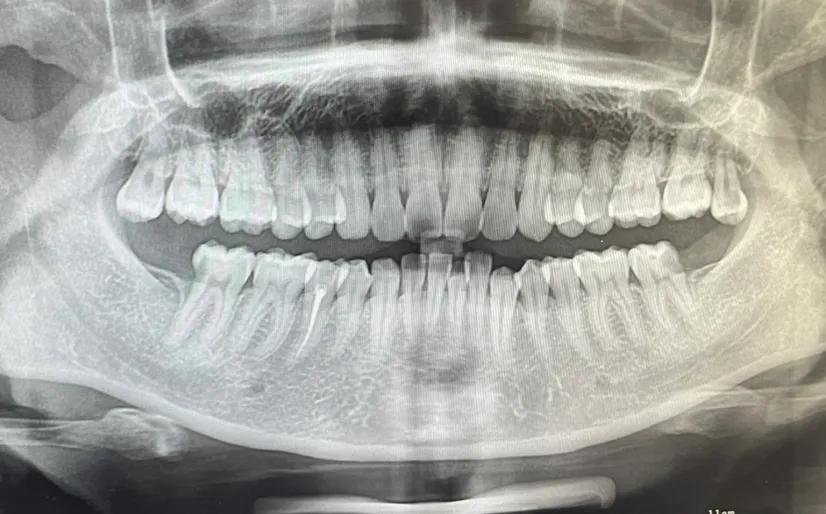

这次这颗坏牙中间裂开了,我就下定决心一定要去好好整整我的牙,不管付出多大的代价,只要它不再折磨我了就行!我去的是私人牙科诊所,正好赶上他们店刚新开另一个分店,有活动,我就立刻决定直接种植牙,顺带着给另外一颗牙做了根管治疗。费用总共加起来7000元。不是太贵吧。